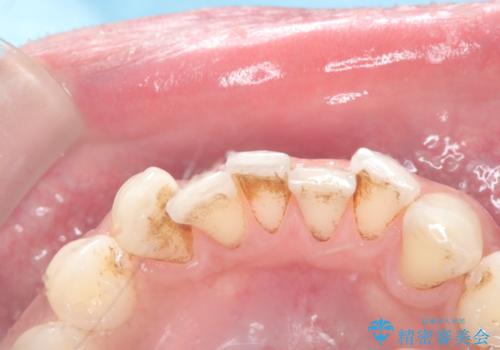

歯の着色にはエアーフロー

- 治療計画

- 濃い着色はホワイトニングでは落ちないためエアーフローをお勧めいたします。定期的にホワイトニングをやっているので白さはキープしていた方なので仕上がりは綺麗になりとてもご満足いただけました。

着色が付きやすい飲み物や歯並びなどの原因もあることもアドバイスさせていただきました。

PMTCのブラシが入りづらい歯間部にもエアーフローは対応できより綺麗になります。

歯に付着しているバイオフィルムも落とすことができ、状態によっては染め出しを行いみていただきながらやっています。